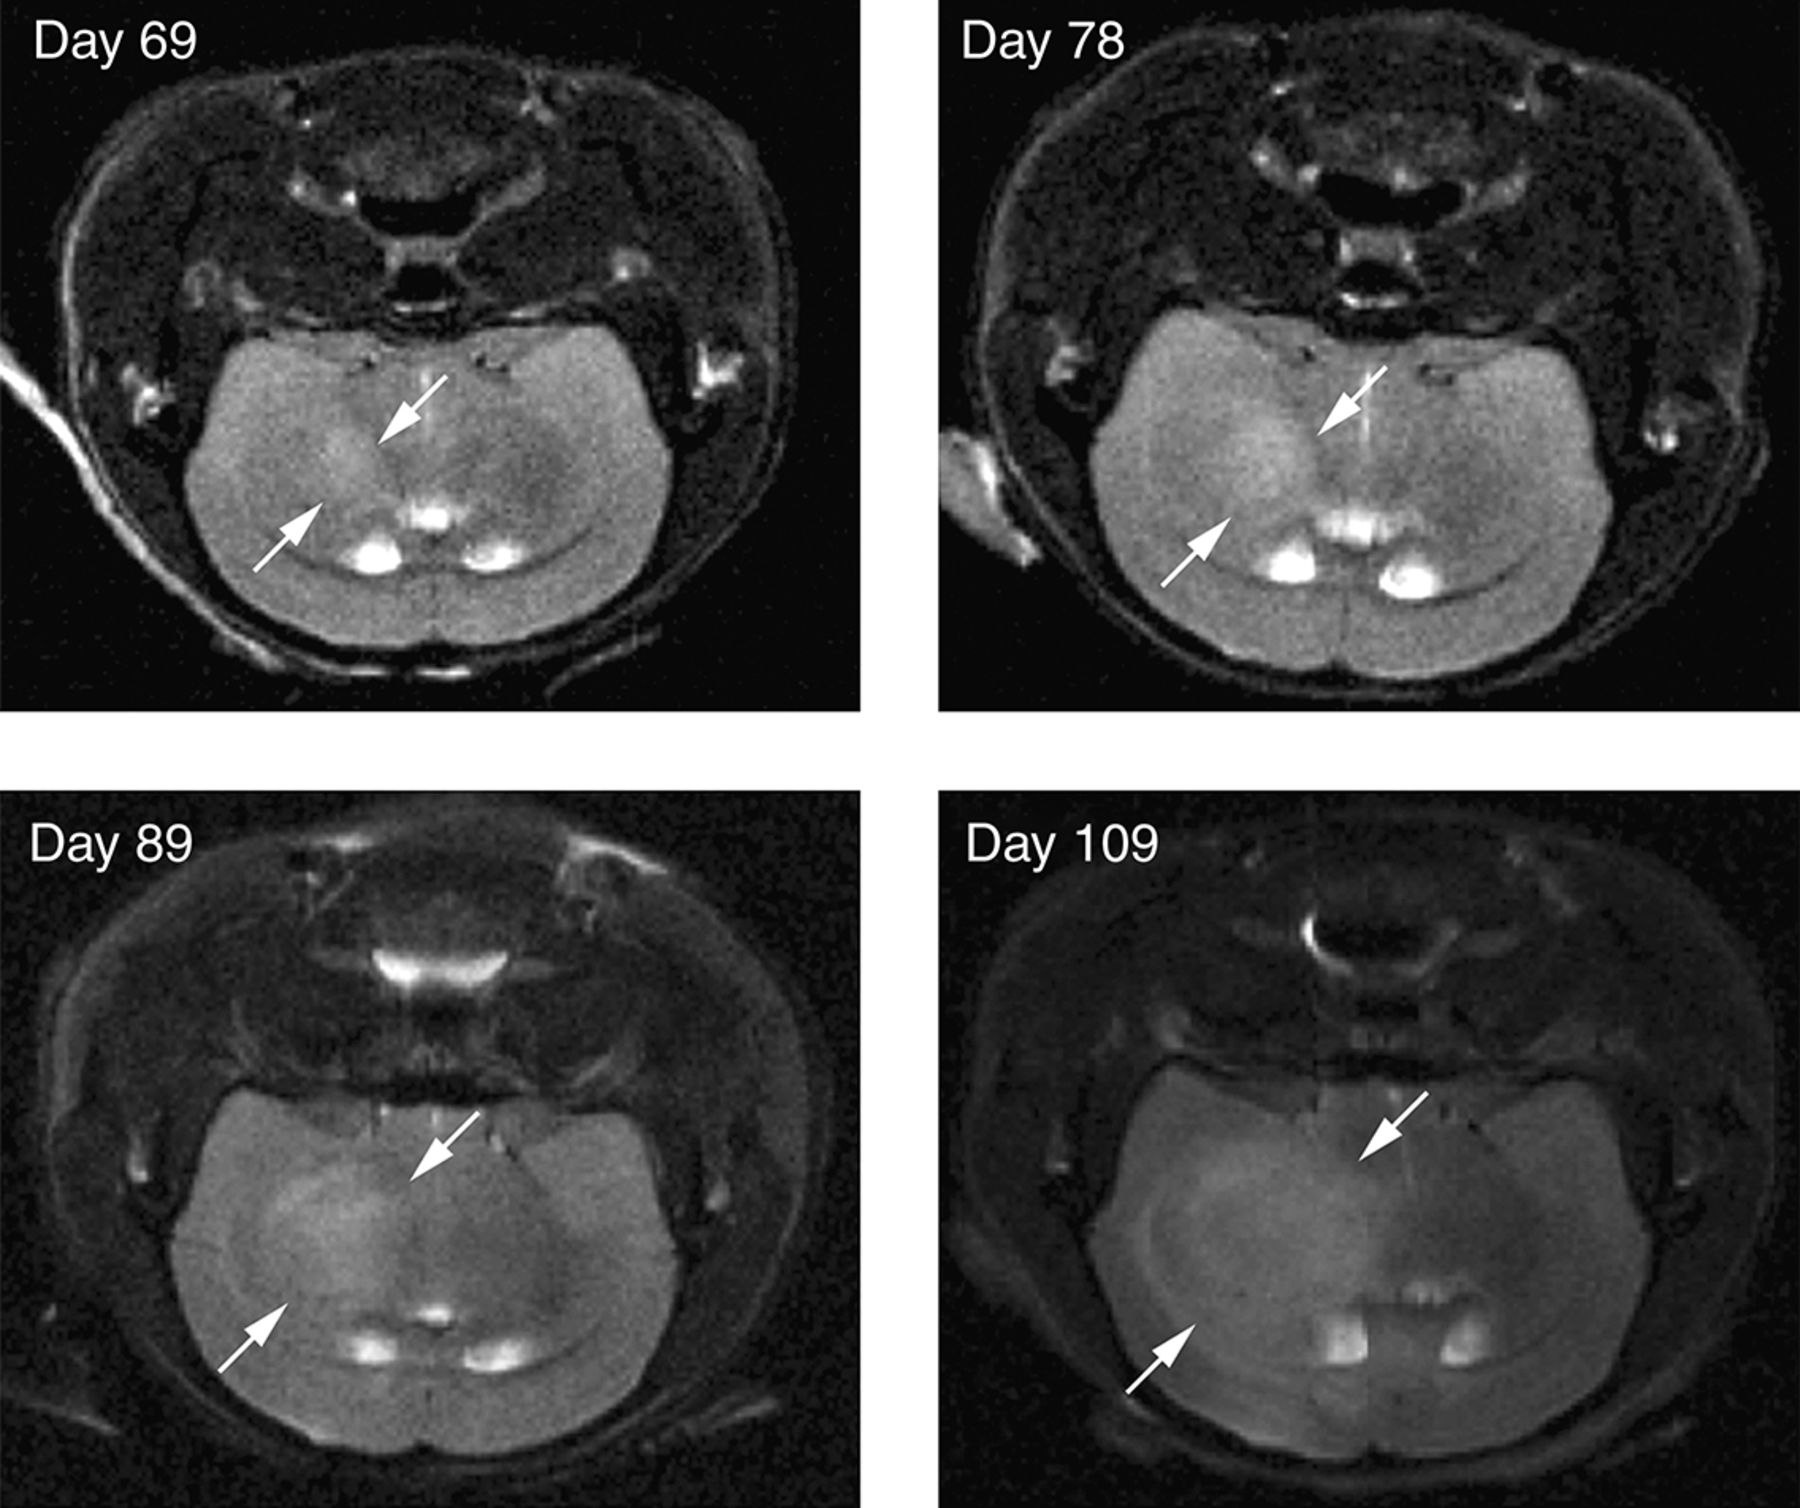

Figure 2.

MRI of orthotopic brain tumors. Primary human glioblastoma multiforme cells were stereotactically implanted into the brains of mice. MRI imaging shows progressive growth of primary orthografts at the indicated time after implantation. The tumor (boundary indicated by arrows) is distinguishable from surrounding brain tissue on the basis of T2 hyperintensity (transverse relaxation).